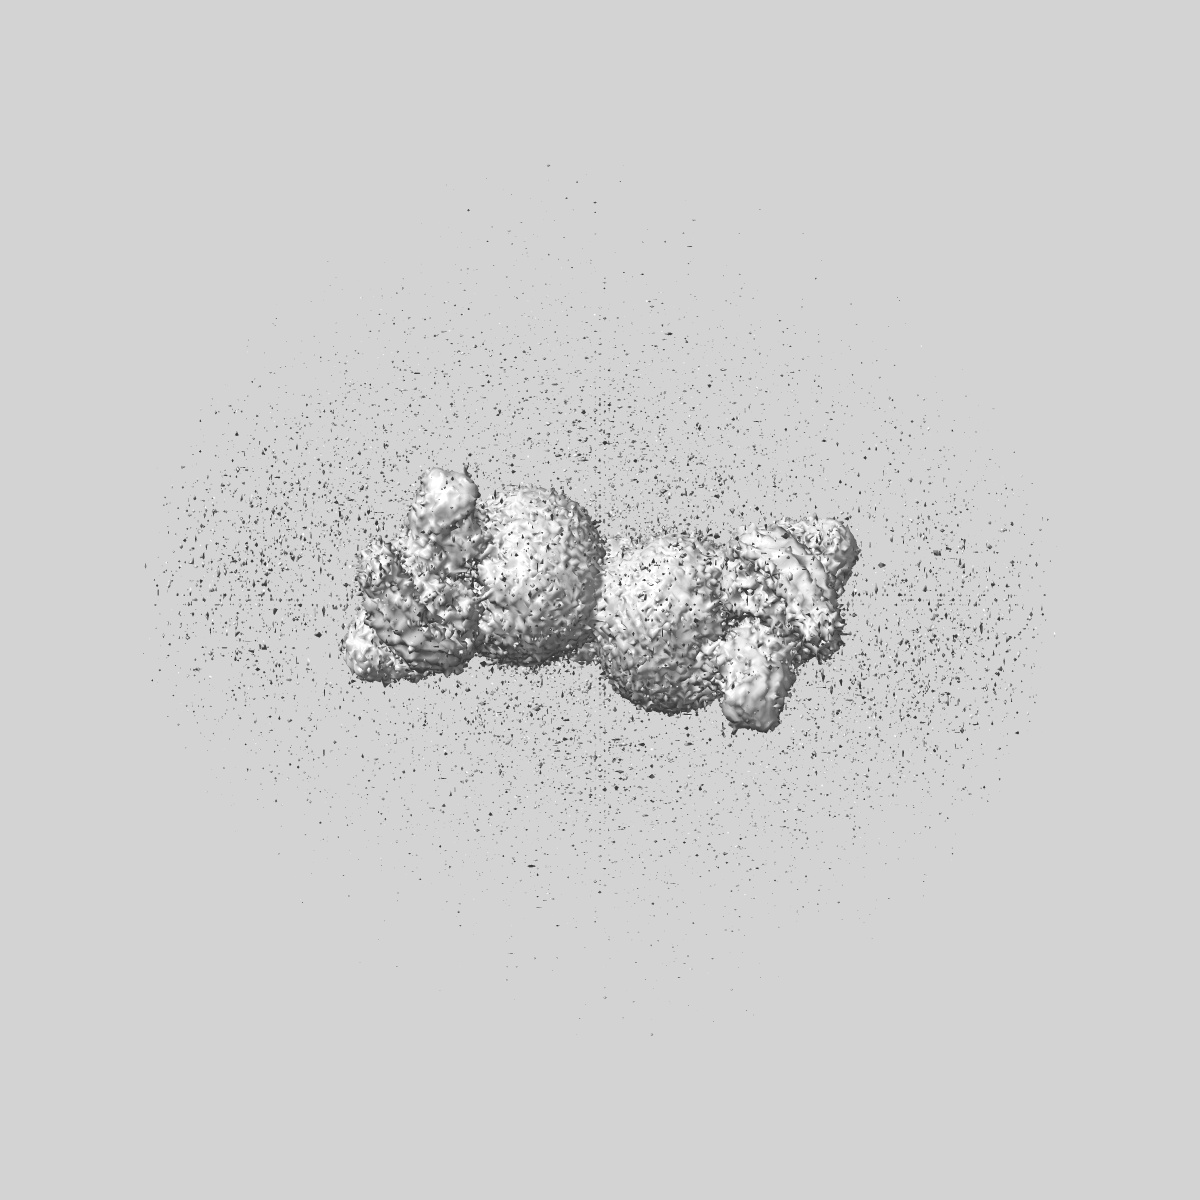

Structure of CXCR2 bound to CXCL5 (CXCR2-CXCL5-Go Full map)

Single-particle3.32 Å

Sample: C-X-C chemokine receptor type 2 in complex with C-X-C motif chemokine 5 and Go

Molecular basis of promiscuous chemokine binding and structural mimicry at the C-X-C chemokine receptor, CXCR2.

(2025) Mol Cell , 85 , 976 - 988.e9